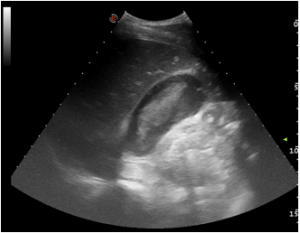

He went on to have emergency CT (figure 4) prior to surgery. The patient underwent midline laparotomy with repair of liver laceration and gallbladder. Leakage of bile and blood around the gallbladder was found during surgery. He had an uneventful post-operative course and was discharged on the seventh postoperative day.”

The authors go on to further describe the pericholecystic fluid evaluation in abdominal trauma and that the gallbladder can get injured.